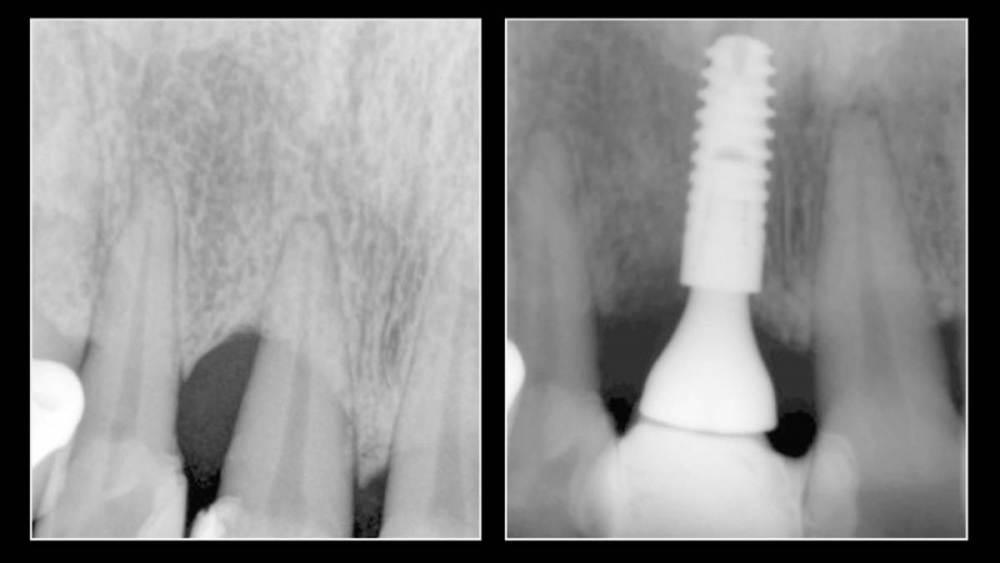

Владмир Опубликовано 20 марта, 2023 Автор Поделиться Опубликовано 20 марта, 2023 Здравствуйте коллеги. Работе 10 лет. Фото начальных этапов добавил 7 1 2 Ссылка на комментарий